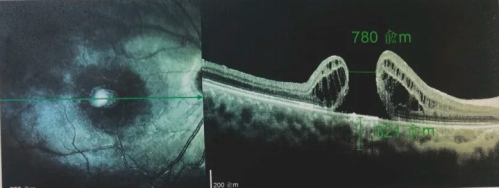

由于自身患有頸椎病,每次術(shù)后長(zhǎng)期的趴睡都讓他痛苦不堪。為了尋求更好的治療,吳爺爺來(lái)到廈門(mén)大學(xué)附屬?gòu)B門(mén)眼科中心,找到了眼外傷及眼底病2科的李海波博士后。此時(shí),吳爺爺右眼的黃斑裂孔已經(jīng)持續(xù)擴(kuò)大到780μm,演變?yōu)殡y治性的大裂孔。

最讓吳爺爺難以置信的是:術(shù)后只需保持平躺24小時(shí)!第二天復(fù)查時(shí),眼底鏡及OCT檢查清晰顯示——那個(gè)折磨了他大半年的大裂孔,竟然閉合了!且吳爺爺?shù)挠已垡暳τ辛嗣黠@的改善,術(shù)后3天已經(jīng)可以看到 0.15。